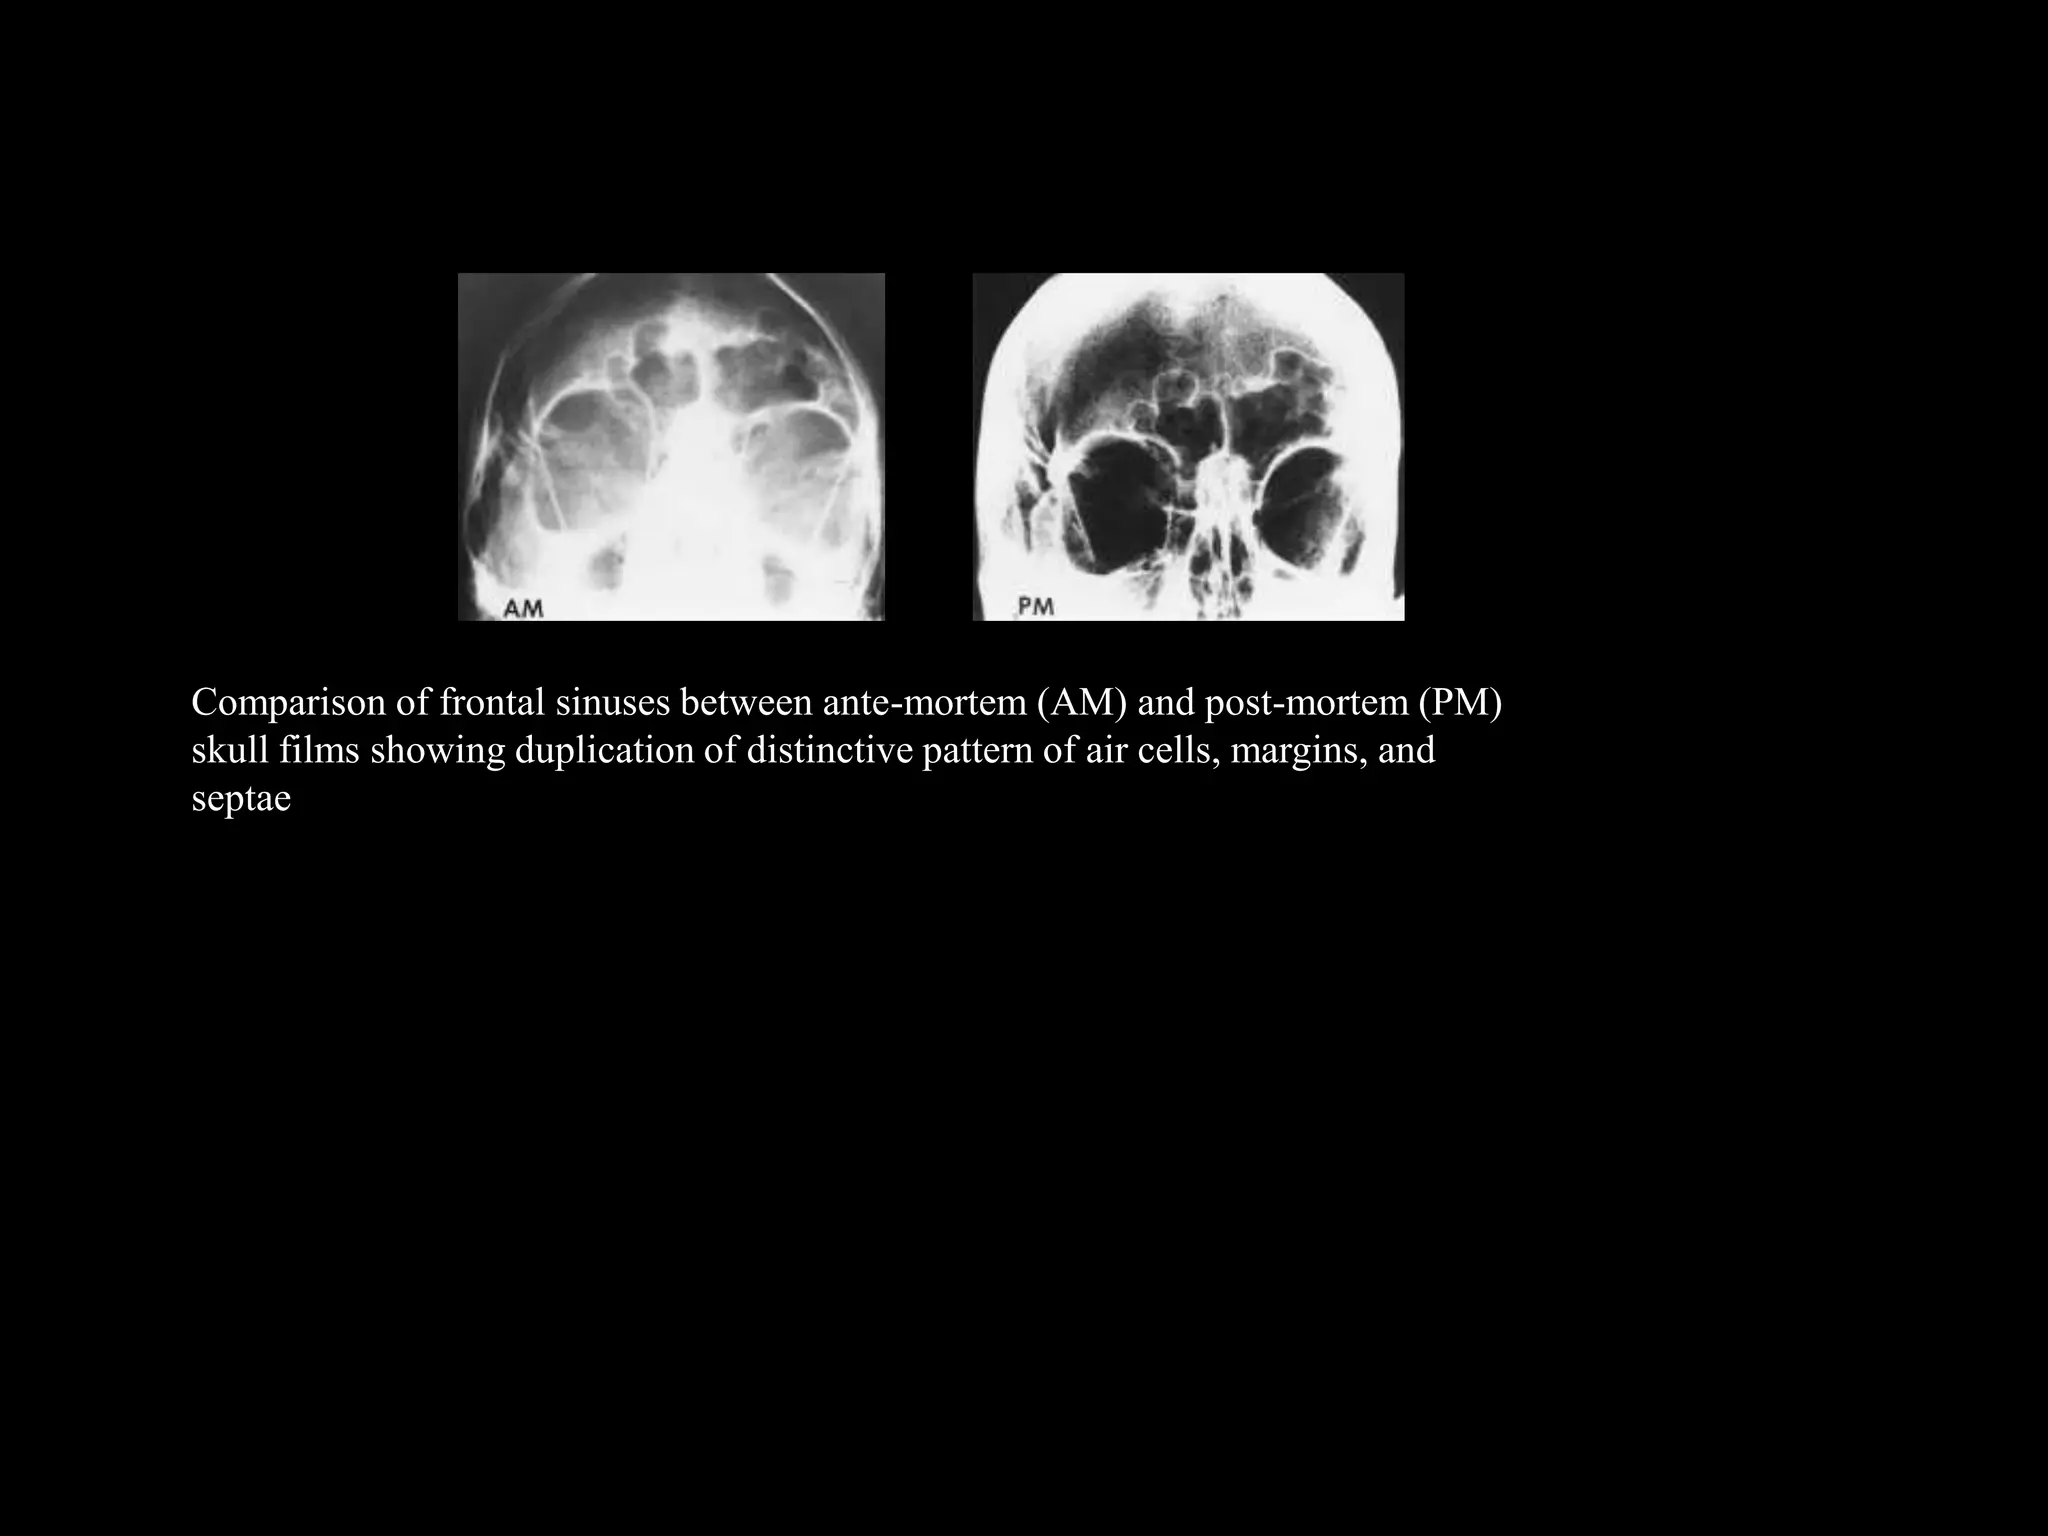

– Radiographic identification is often conclusive.

7. Bone pattern – Medullary bone, max. sinus

configurations